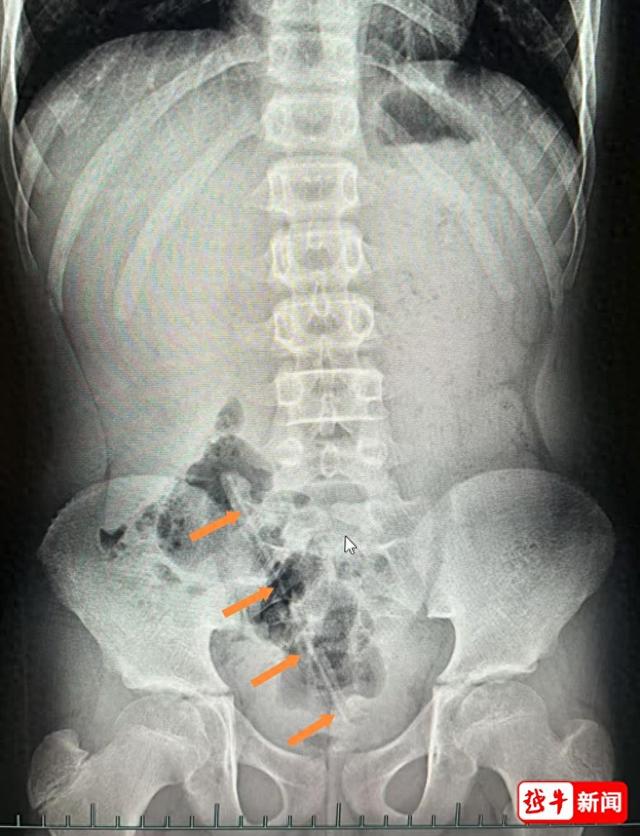

小兒外科醫生屠菊英查體時在患兒右側臍旁觸及一條狀物體,但肛門指檢卻未能探及異物。急診腹部X線檢查顯示:盆腔內確有一條狀異物,長度約17cm。

小木塞進肛門裡的鉛筆↓